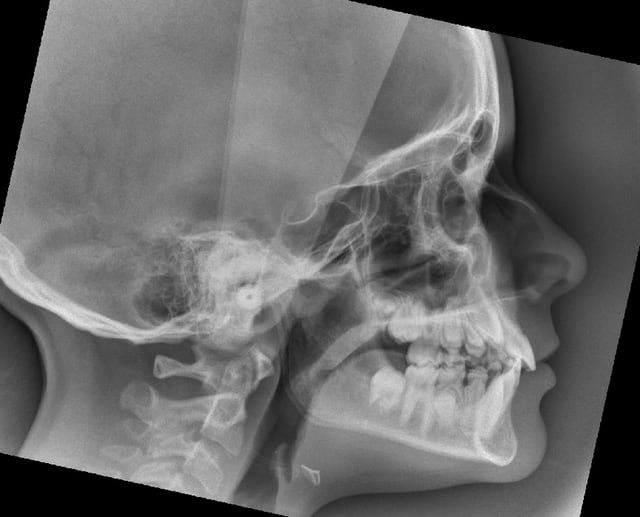

TELE DE PROFIL

je me lance: ta patiente est méso tendance brachy, avec une classe 1 squelettique limite. Elle présente par contre un maxillaire en V avec des 6 sup en rotation. Elle a aussi certainement un problème fonctionnel vu la langue basse et les amygdales fortes. Pour ma part je verrais le problème odf dans son ensemble avant de penser à la 13. Je propose donc: quad helix pour reformer le maxillaire puis levé de la supraclusion par un bionator ou une enveloppe linguale nocturne. Puis réévaluation, la classe 2 dentaire devrait être passée en classe 1 si tout va bien et le multibagues devrait permettre d'ouvrir l'espace. Donc pour moi pas d'extraction de suite.

Je pense personnellement que l’urgent, c’est cette 13.

Il semble bien qu’elle soit en train de partir vers l’inclusion palatine, sa couronne déborde déjà la 11 (en vestibulaire, elle apparaîtrait plus horizontale sur le téléprofil).

Je te conseille de supprimer 52 et 53 rapidement pour qu’elle ait des chances de reprendre un chemin d’éruption correct.